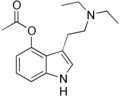

| 4-Acetoxy-DET | artificial | 4-OCOCH3 | CH2CH3 | CH2CH3 | 4-acetoxy-N,N-diethyltryptamine | 1135424-15-5 |